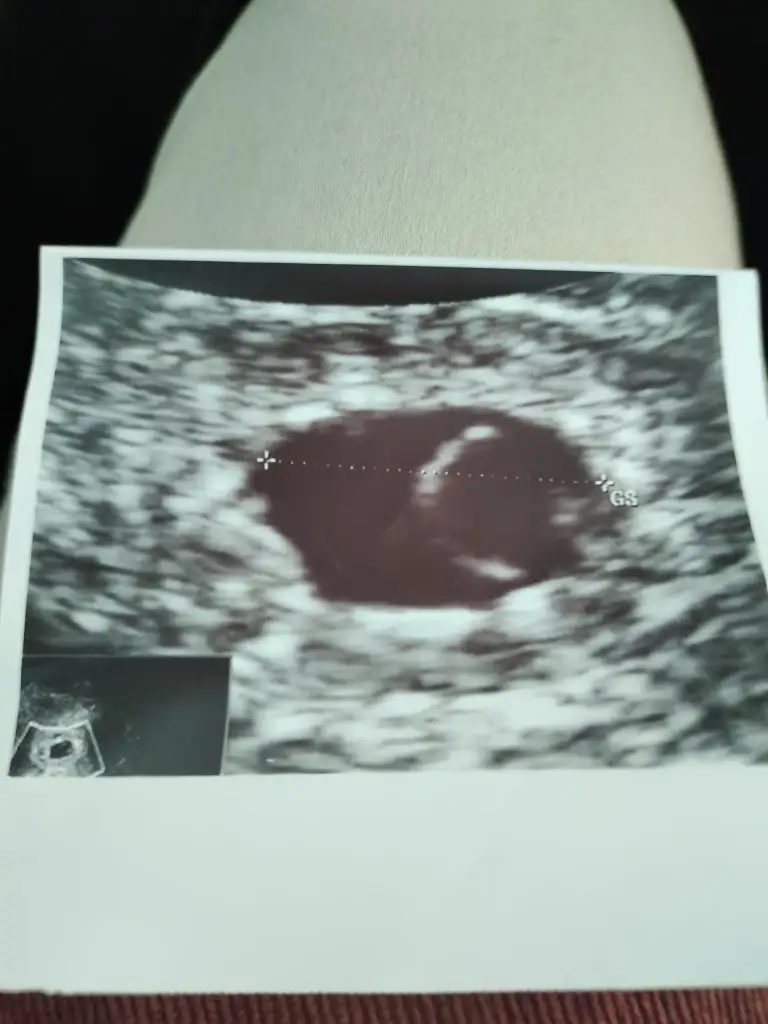

Kızlar bugün keseyi gördük çok şükür 😇 ama 5+6 olması gerekirken 5+1 göründü vajinal USG de normal mi sizce sat 18 kasim transfer tarihi 7 Aralık çift transfer olmuştum 5.gun embriyosu tek kese göründü bide 🥰 inşallah kalp atışı ni da duyarım haftaya ❤️

Hayırlı olsun canım keseyle bebişi de görmüşsün çok şükür 🙏 normal ultrasonda öyle olması benim de bir iki gün geriden geliyor. Bu dönemde değişiklik olurmuş haftadan haftaya